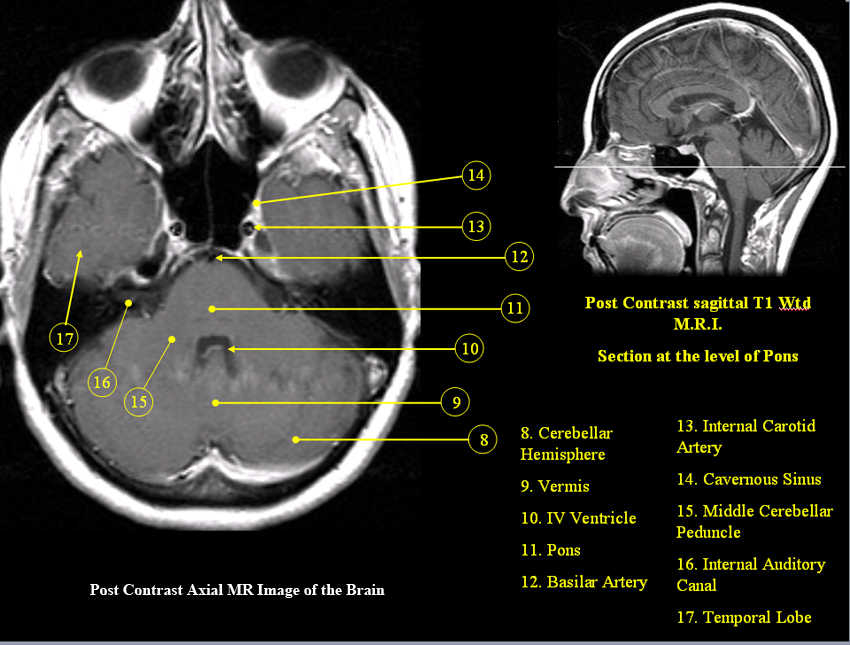

MR Brain and Spine